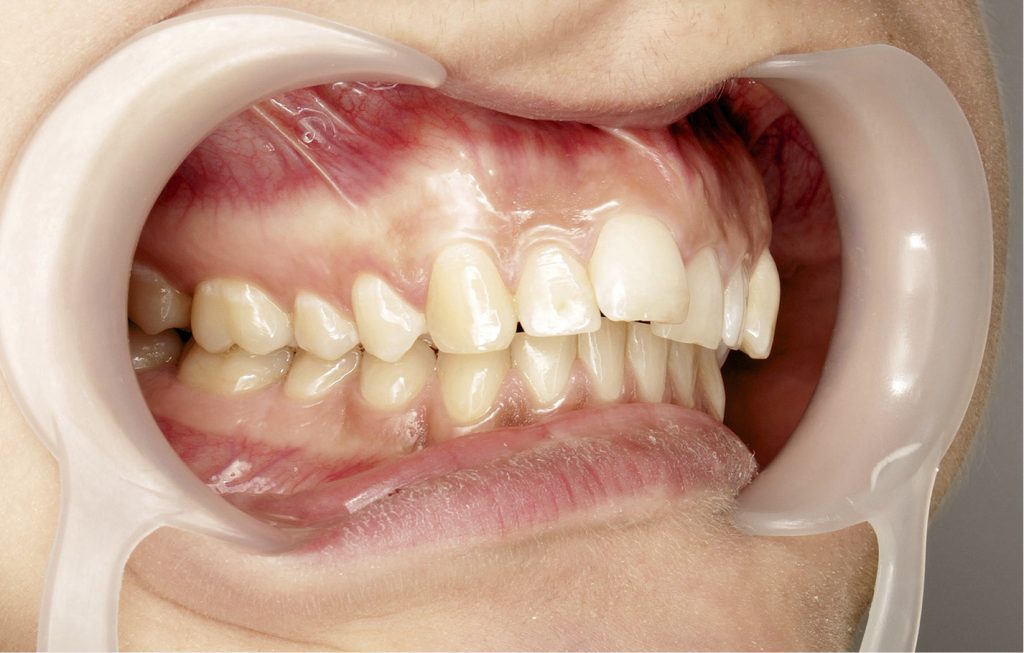

Streszczenie: Tyłozgryz jest najczęściej występującą wadą zgryzu wśród pacjentów leczących się ortodontycznie w populacji polskiej. Wpływa ona na pogorszenie profilu twarzy wynikające z dotylnej pozycji żuchwy, dolnego łuku zębowego lub kombinacji obu. Leczenie wady opiera się na analizie wielu czynników, takich jak: wiek pacjenta, nasilenie wady, typ wzrostu, typ profilu, dyskrepancja zębowo-wyrostkowa, motywacja pacjenta oraz umiejętności lekarza. Wady dystalne u pacjentów rosnących mogą być leczone przez modyfikację wzrostu przy użyciu aparatów czynnościowych. Natomiast u pacjentów dorosłych leczenie często wiąże się z ekstrakcjami pierwszych zębów przedtrzonowych w szczęce, retrakcją kłów do I klasy oraz zębów siecznych w miejsce poekstrakcyjne kamuflujące wadę. Przy skrajnych przypadkach proponowana jest także operacyjna korekta wady. Te metody postępowania wiążą się z wydłużeniem czasu terapii. Proponowanie takich rozwiązań może spowodować, że pacjent nie zaakceptuje planu leczenia. Należy wtedy zaproponować alternatywne leczenie, polegające na dystalizacji całego górnego łuku zębowego. Celem pracy jest przedstawienie dynamiki zmian u dorosłej pacjentki ze zdiagnozowaną wadą klasy II grupy 1 (protruzją zębów siecznych), leczoną aparatem stałym, bez ekstrakcji, wykorzystując miniimplanty ortodontyczne w celu dystrakcji łuku zębowego szczęki.